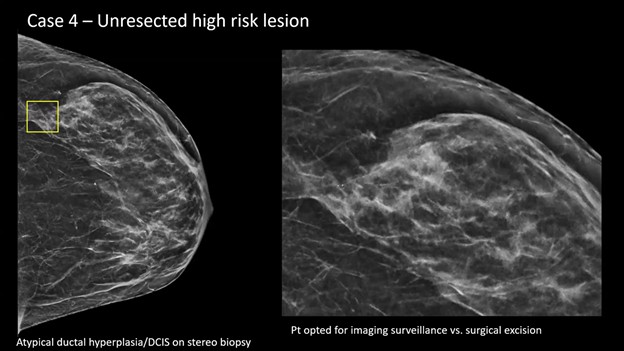

Presentation—A screening mammogram revealed subtle calcifications in the lateral aspect of the breast (yellow box). After magnification and stereotactic needle core biopsy, the pathology returned as atypical ductal hyperplasia (ADH), suspicious for ductal carcinoma in situ (DCIS).

Management Dilemma—Typically, surgical consultation and excision are recommended for this pathology. However, in this case, patient and surgeon alike opted for surveillance, instead of excision.

Reporting the Follow-Up—When a patient with an unresected high-risk lesion returns for surveillance (e.g., 6 months to 1 year later), your goal is active monitoring. Step 1: identify the titanium biopsy marker (yellow box) . . .

Step 2? Check for changes. Specifically, you’re looking for residual calcifications or any new areas of calcification.